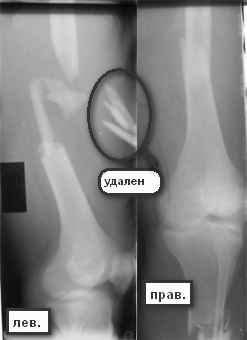

Больной 29 л 23 февраля на мопеде въехал в легковой автомобиль (естественно, больной пьяный). Поступил с диагнозом: закрытый перелом правого бедра в с/з-н/з, открытый перелом правой голени в в/з (рана в проекции перелома до 3 см), открытый оскольчатый перелом левого бедра в с/з с дефектом костной ткани (рана до 12 см по наповерхности бедра). ПО дежурству - ПХО ран, стержневые аппараты на оба бедра, аппарат Илизарова на правую голень. По стабилизации состояния - домонтаж аппарата Илизарова с окончательной репозицией. Спустя 2 недели - открытая репозиция отломков правого бедра, интрамедуллярный остеосинтез стержнем с дистальным блокированием. С правой ногой разобрались. Вопрос встает о том что делать с левой. При ревизии раны левого бедра (при поступлении) удален торчащий из раны свободный осколок до 6х3 см,загрязненный травой,пылью.Со слов скорой - на месте происшествия вроде как были еще мелкие костные осколки. Осколки что на снимке лежат по внутренней поверхности бедра, связаны с м/тканями, дефект кости до 7-8 см по длине. Массы осколков явно не хватает для его заполнения. Кроме того массивное скелетирование основных отломков (до 7-10 см в обе стороны). Все раны зажили без проблем. Наши планы - открытая репозиция левого бедра, ИМО с укорочением. Потом когда (если)срастется пусть занимаются реконструктивными операциями. Буду рад услышать ваши мнения, предложения по данному случаю.С уважением А. В. Л.